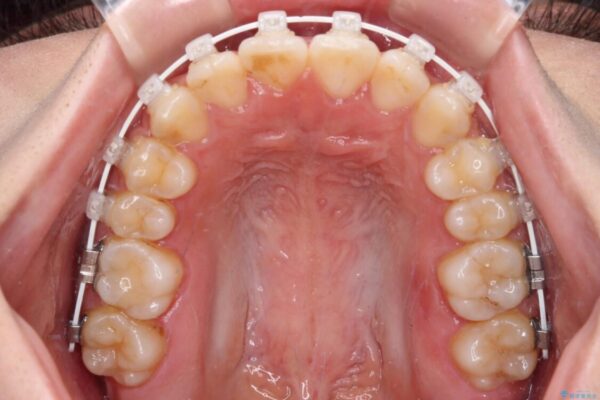

治療途中

• 【モニター】短期間で終わりたい ワイヤー装置での非抜歯矯正 治療途中画像